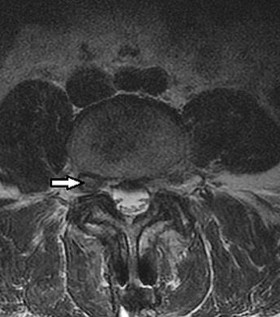

A 55-year-old diabetic male presents with severe mid-thoracic back pain, subjective fevers, and progressive bilateral leg weakness over the past 24 hours. His CRP is 120 mg/L.

An urgent MRI demonstrates a ventral spinal epidural abscess at T8-T10. Which of the following constitutes an absolute indication for urgent surgical decompression?

Explanation

A 60-year-old male with poorly controlled diabetes mellitus presents with severe back pain, fever, and progressive bilateral lower extremity weakness over the past 24 hours. An urgent MRI confirms an anterior epidural abscess at L2-L3.

Blood cultures are drawn. What is the next best step in management?